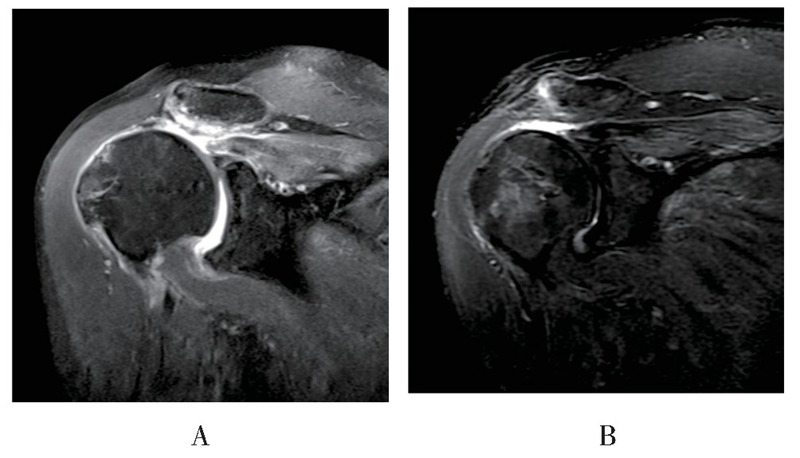

MRI随访见18例患者重建组织结构完整,愈合率达85.7%(18/21),3例出现明显结构失败,但失败患者功能恢复良好,未诉明显不适,因此未行翻修手术(见图5、图6)。

图6 患者男,56岁,术后6个月随访时斜冠状位MRI显示右肩术后重建结构失败A:术前磁共振影像,B:术后磁共振影像